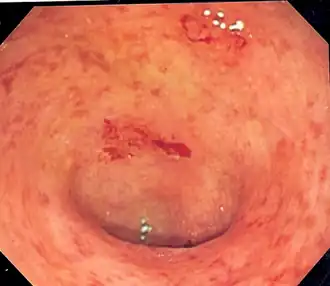

В острой стадии язвенного колита отмечаются экссудативный отек и полнокровие слизистой оболочки с утолщением и сглаженностью складок. По мере развития процесса или перехода его в хронический нарастает деструкция слизистой оболочки и образуются изъязвления, проникающие лишь до подслизистого или, реже, до мышечного слоя. Для хронического язвенного колита характерно наличие псевдополипов (воспалительных полипов). Они представляют собой островки слизистой оболочки, сохранившейся при её разрушении, или же конгломерат, образовавшийся вследствие избыточной регенерации железистого эпителия.

Постановка диагноза язвенный колит в большинстве случаев не вызывает затруднений. Клинически он проявляется наличием крови и слизи в стуле, учащение стула, болью в животе. Объективное подтверждение диагноза происходит после проведения фиброилеоколоноскопии с осмотром подвздошной кишки и гистологическим исследованием биоптатов, до этого момента диагноз является предварительным. Наиболее характерными эндоскопическими признаками являются непрерывное воспаление, ограниченное слизистой оболочкой, начинающееся в прямой кишке и распространяющееся проксимальнее, с четкой границей воспаления.[13]